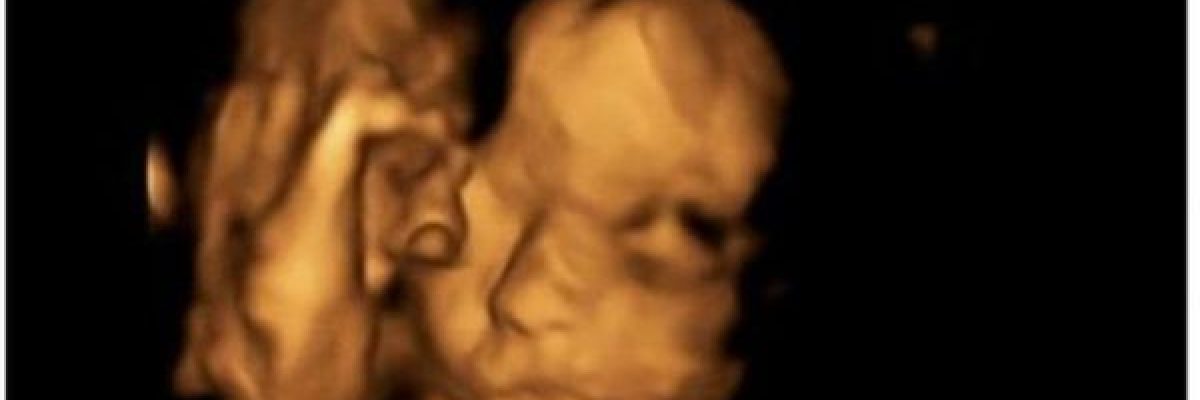

اجرى اطباء بريطانيون عملية في العمود الفقري لجنين بينما كان لا يزال في رحم امه.

وقد فتح الرحم خلال العملية التي استمرت 4 ساعات، وتمكن الاطباء من اجراء رتق في الجزء الخلفي من العمود الفقري.

وفتح الرحم خلال العملية الجراحية التي اجريت في الاسبوع الرابع والعشرين من الحمل ورفع الجنين في وضع يسمح بالوصول الى عموده الفقري واجراء الجراحة ومن ثم اعادة الحبل الشوكي الى مكانه.